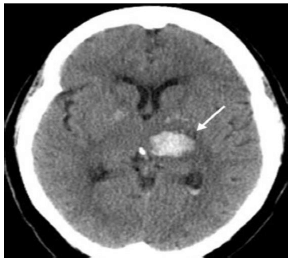

Paciente de 65 anos, do sexo masculino, com antecedente de hipertensão arterial mal controlada e diabetes, é admitido na UTI com o diagnóstico de acidente vascular cerebral hemorrágico de etiologia hipertensiva.

Ao ser admitido, apresenta-se em Glasgow 15, hemiplégico à direita, disártrico e com paralisia facial de padrão central, sem outras alterações ao exame neurológico. Encontra-se ainda com FC 65, PA 190x110, FR 18, SatO2 97% em ar ambiente e com glicemia capilar de 350mg/dL.

A imagem a seguir ilustra uma tomografia de crânio realizada no Pronto Socorro.

Na prescrição deste paciente da UTI devem constar os seguintes itens, à exceção de um. Assinale-o.